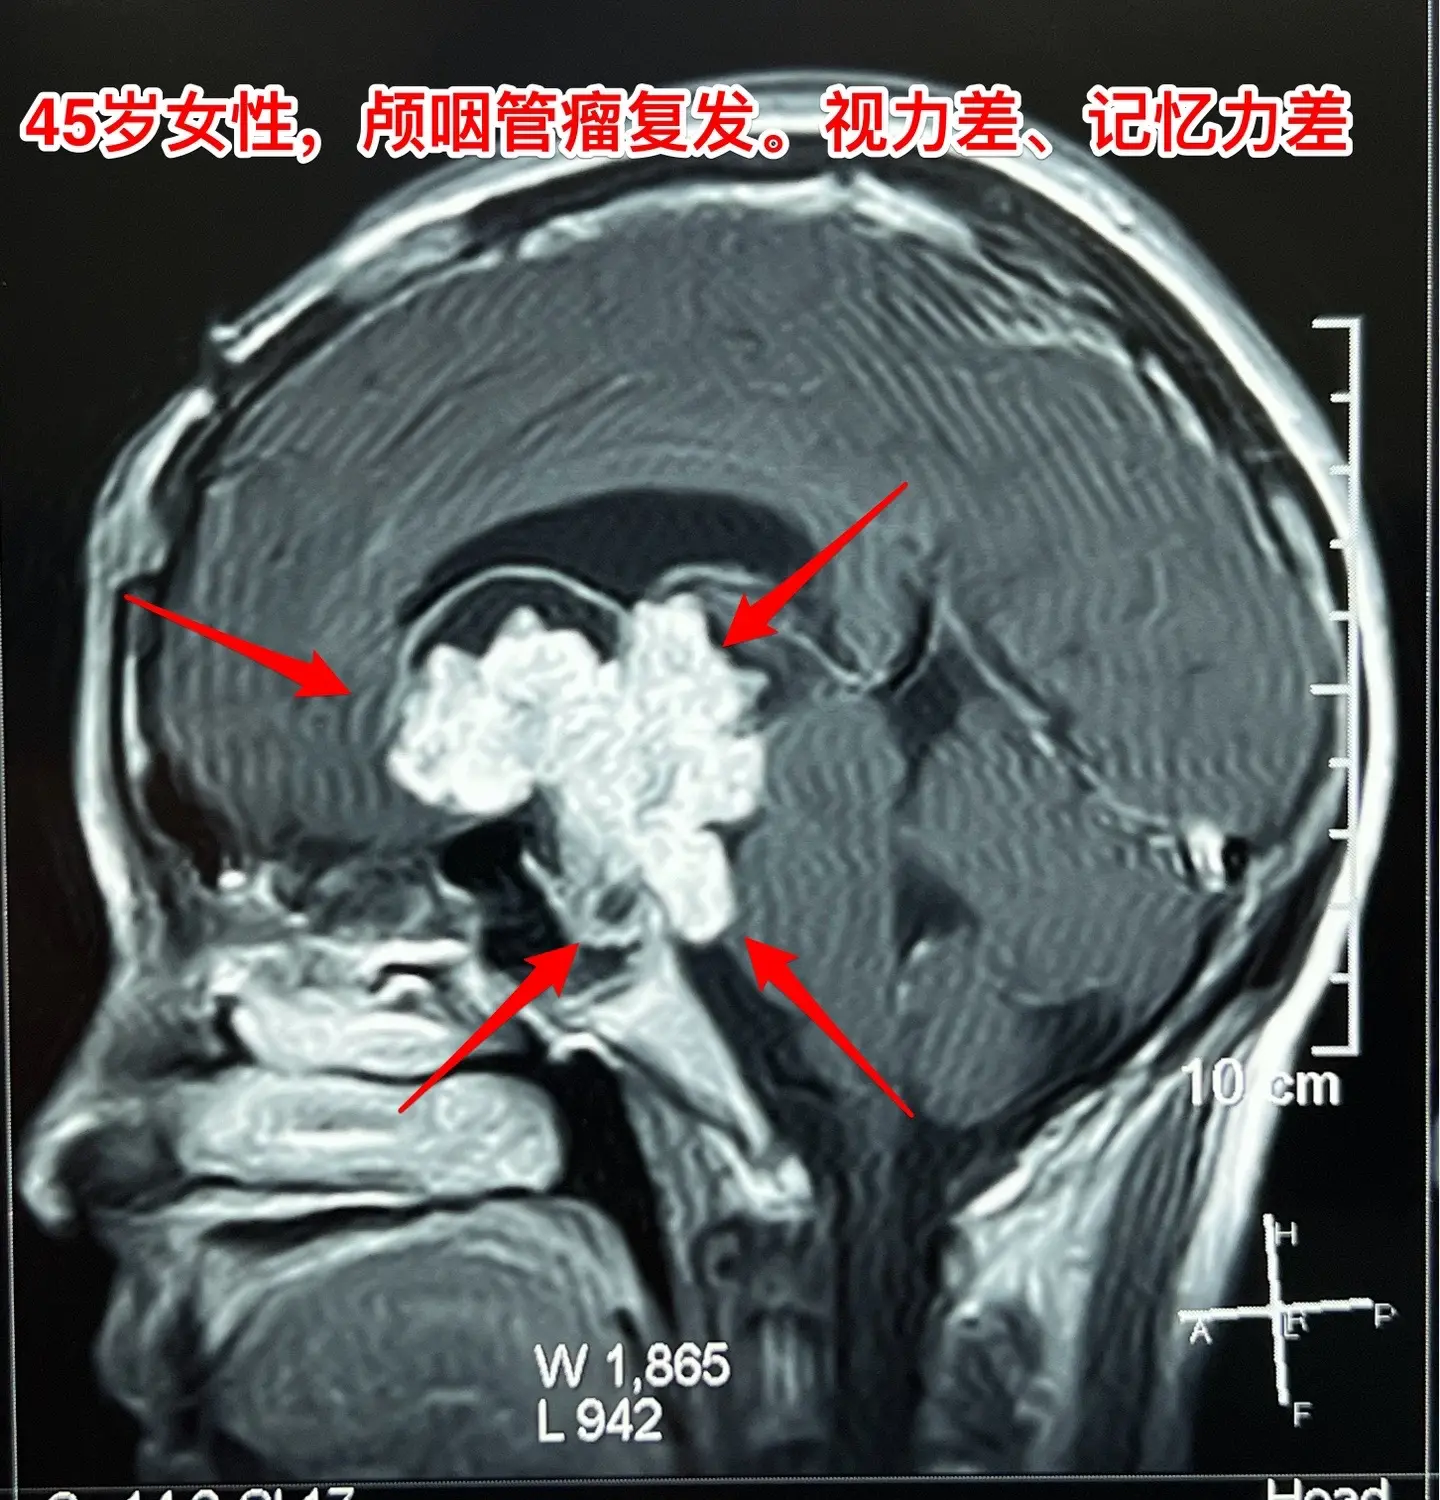

巨大的颅咽管瘤。45岁浙江女性,在外院作了颅咽管瘤手术不到一年,作磁共振显示肿瘤复发,而且体积巨大。 病人视力很差,记忆力也差,精神不好。 这么大的颅咽管瘤一般是需要作手术的。显而易见是这样的手术是很有难度的,很考验医生的技术和能力! 从影像学资料可以看出,这是乳头型颅咽管瘤。如果害怕作手术,对于运气好、经济状况好的病人,也可以试一试靶向药,也许有效。 这个病人选择了作手术!8月16日我们经过九个小时的紧张奋战,将肿瘤完全切除了。手术后CT结果很好。